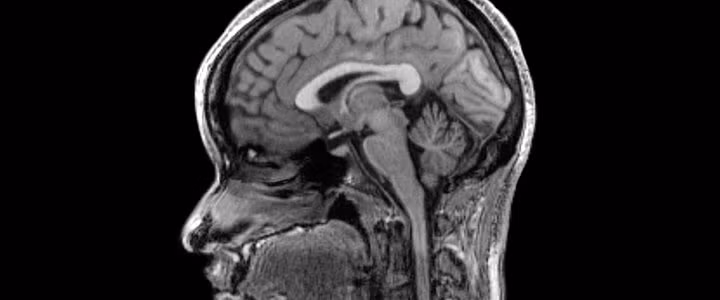

Việc có ý thức cũng mang đến cả cảm xúc, và không hẳn lúc nào chúng ta cũng cảm thấy vui vẻ. Bên cạnh đó, cái giá để có được suy nghĩ cũng tiêu hao rất nhiều tài nguyên và năng lượng của cơ thể. Chúng ta không thể nhịn thở quá lâu vì các neuron sẽ chết do chúng rất cần oxygen. 1/5 năng lượng chúng ta "đốt hàng ngày" được dùng để nuôi não.